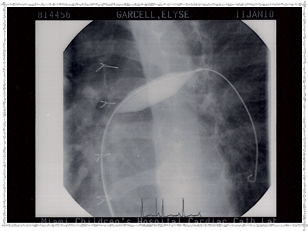

Second Catheterization — Dr. Danyal Khan

In 2010, Elyse underwent her second catheterization procedure, overseen by Dr. Danyal Khan at Miami Children's Hospital. The procedure focused on her pulmonary arteries, and these images show the before and after.

2010 - Pulmonary Artery Ballooned

Pulmonary Artery ballooned